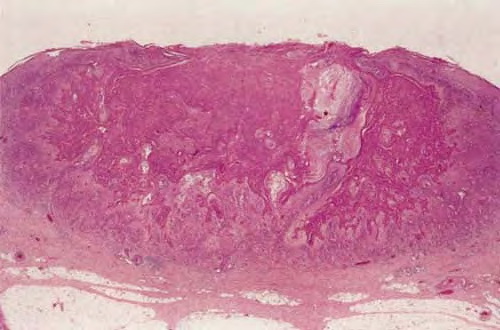

The histopathologic diagnosis of keratoacanthoma rests mainly on the silhouette of the tumor as assessed at scanning magnification; inadequate specimens (i.e., punch biopsies, shave biopsies, curettage) do not allow a diagnosis and differentiation from squamous cell carcinoma. Two large studies on the histopathologic criteria for diagnosis of keratoacanthoma emphasized the overlapping features between this tumor and squamous cell carcinoma, which render differentiation very difficult or even impossible in given cases.

The histopathologic features of keratoacanthoma depend on the stage of evolution of the tumor. In early, proliferative lesions, the epithelium is markedly hyperplastic, and the central keratotic plug is not as pronounced as in fully developed lesions. The lesion has an overall symmetric aspect . Although atypical cells do not represent the majority of the cells in typical keratoacanthoma, there may be atypical keratinocytes and mitoses, especially at the lower margin of the tumor. Nests of epithelial cells may detach from the main tumor mass and be found in the superficial reticular dermis. Fully developed, mature lesions are characterized by a large central core of keratin surrounded by a well-differentiated proliferation of squamous epithelium that in some cases may resemble squamous cell carcinoma . The epidermis at both sides of the central core extends over the keratotic area in a fashion that has been described as “lipping” or “buttressing,” giving a distinct crateriform appearance to the lesion. Nests and strands of keratinocytes may be found apart from the main bulk of the tumor but usually do not extend lower than the level of sweat glands .